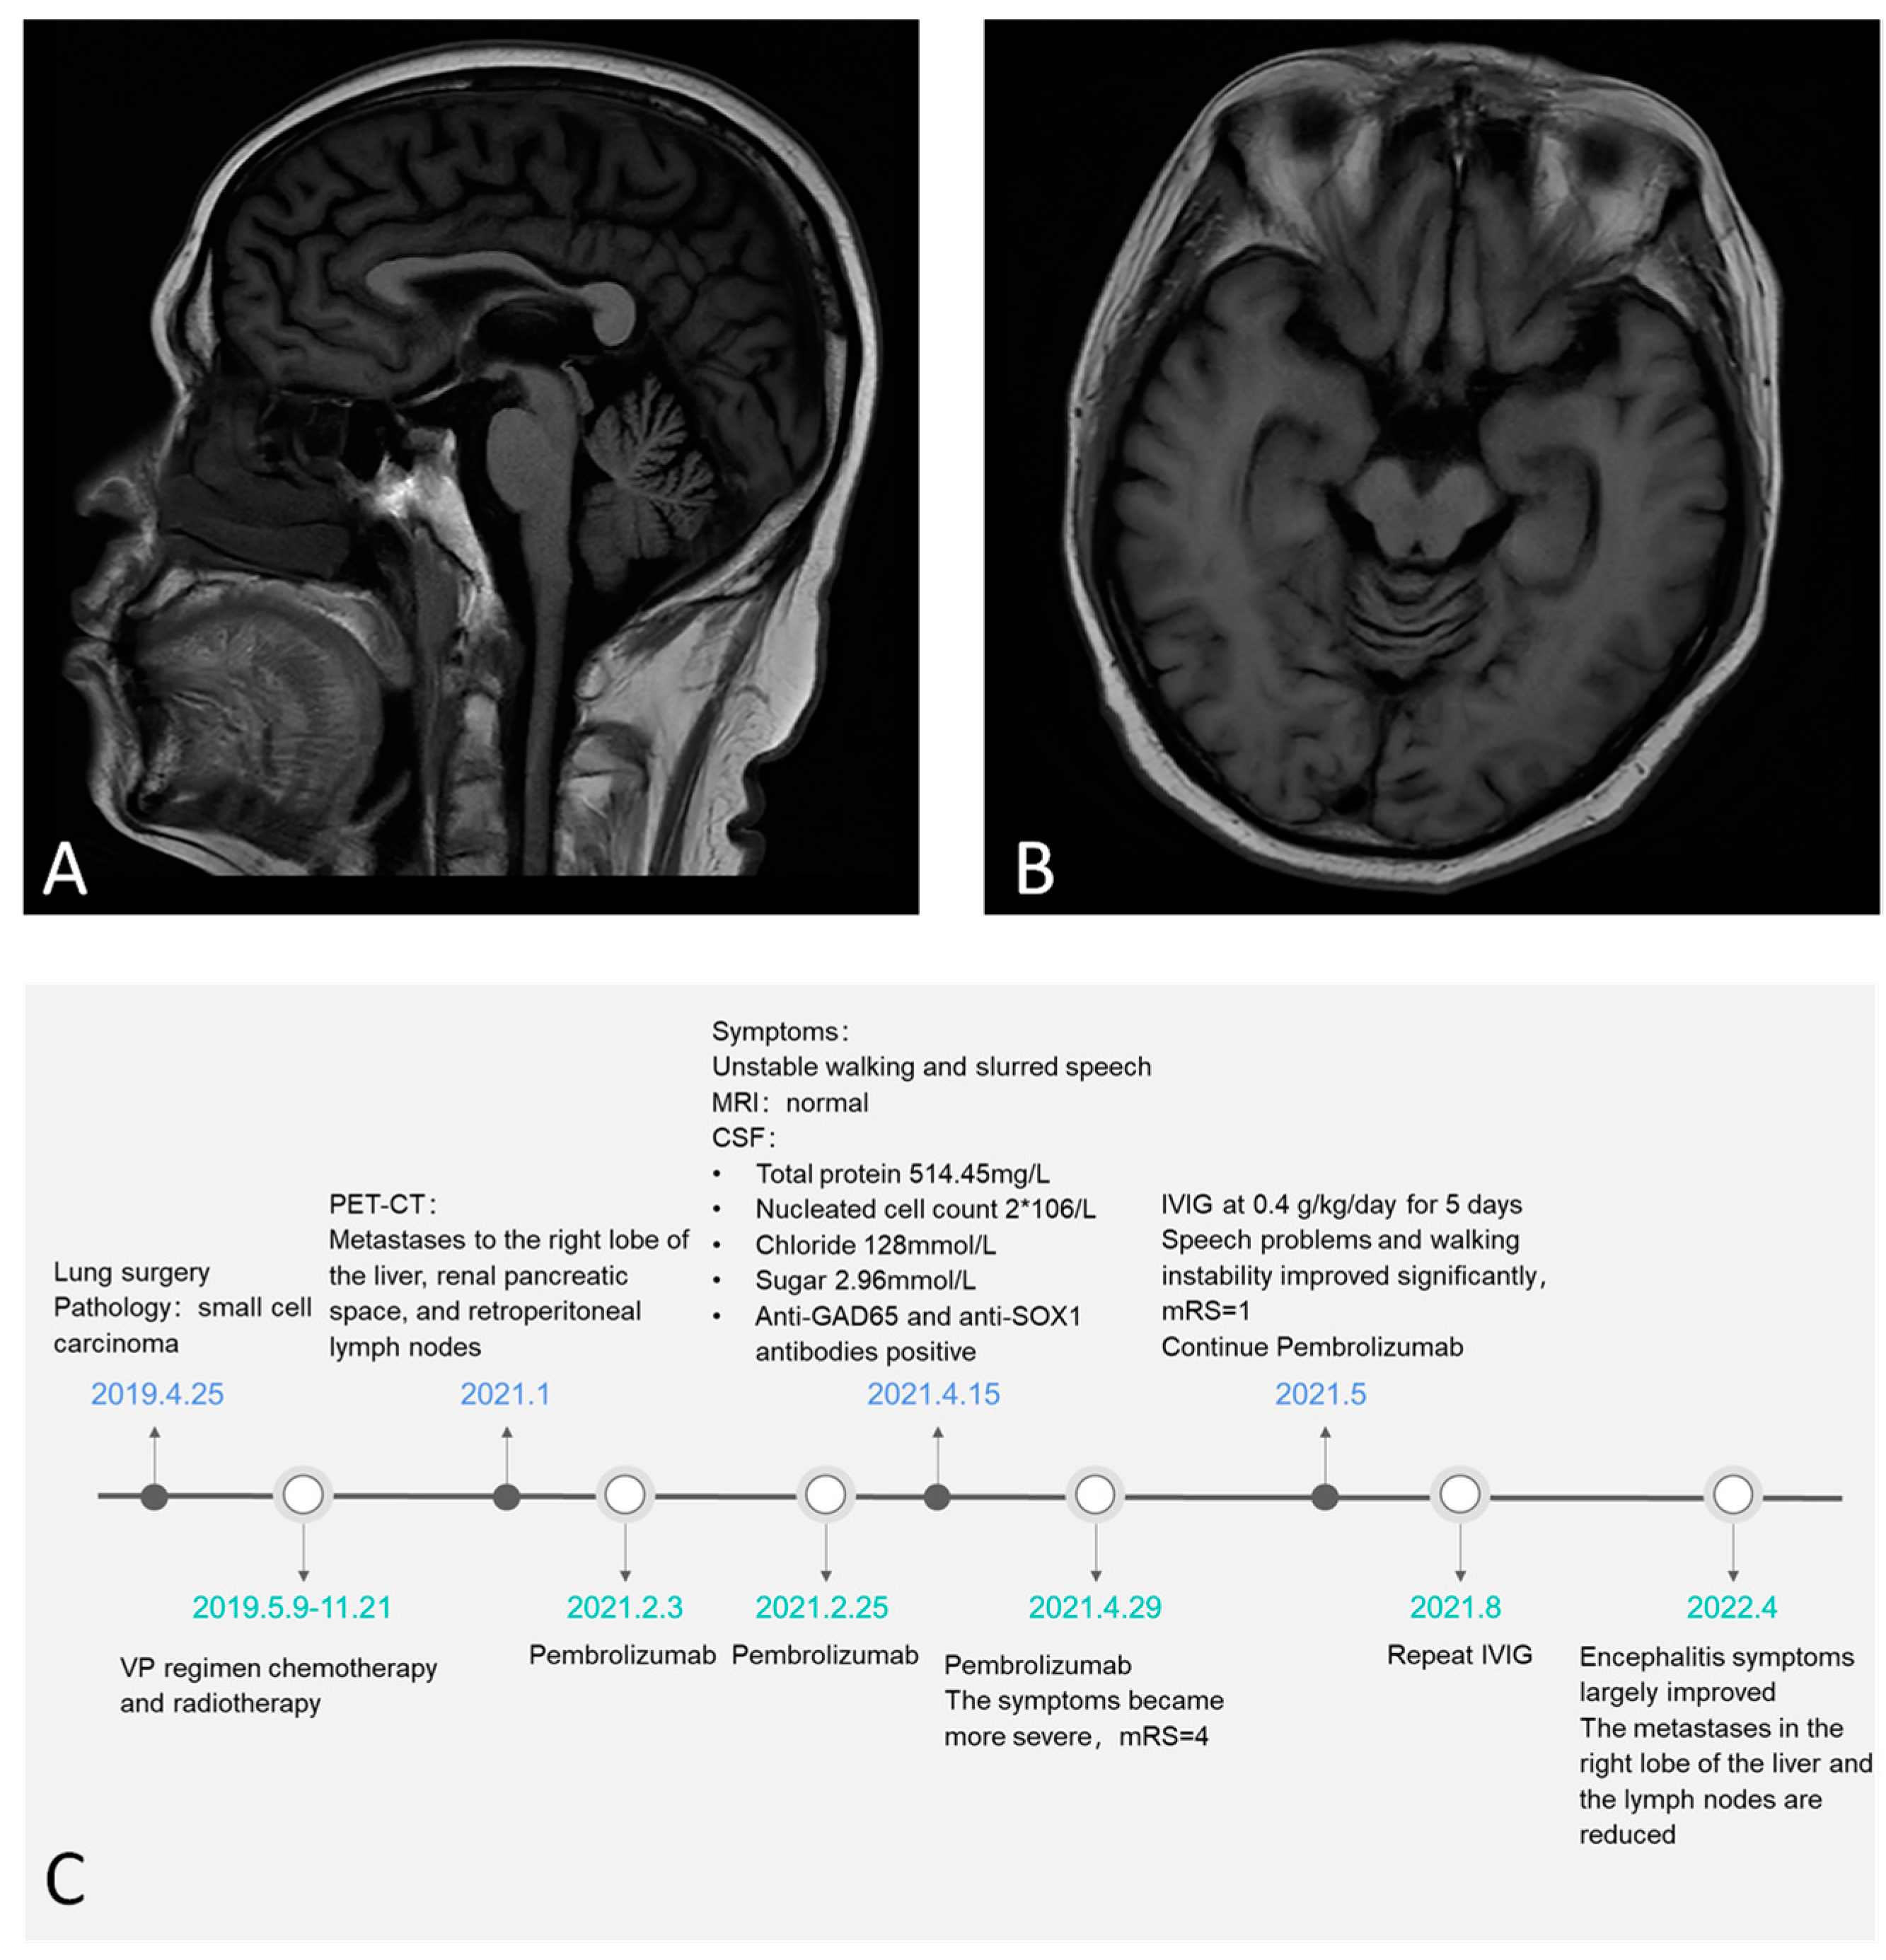

3. Case Report